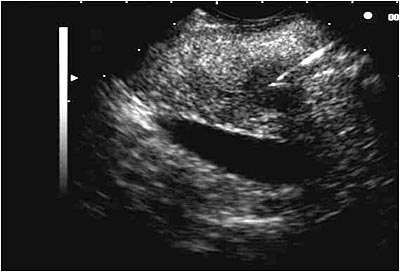

Ultrasound evaluation of the gastro-intestinal tract In more chronic pancreatic disease, the pancreas may be hyperechoic to the mesentery or more often slightly hypoechoic, Pancreatic cancer often has a nodular appearance with mixed echogenicity and absence of pain on transducer pressure. ... Return Doc

SONOGRAPHY Ultrasound Of The Pancreas PANCREAS SPLEEN